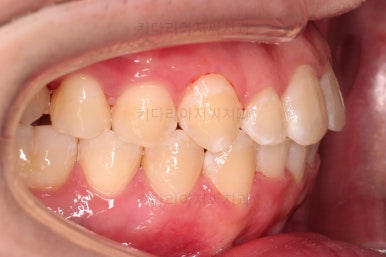

부산교정치과 초진 시 입안의 모습입니다.

앞니가 삐뚤어서 결손치아가 없었더라도 교정치료를 원하셨던 상황이었고요.

오른쪽 어금니 맞물림은 결손치아도 그렇지만 전반적인 앞뒤 차이가 있는 부정교합이 있었어요.